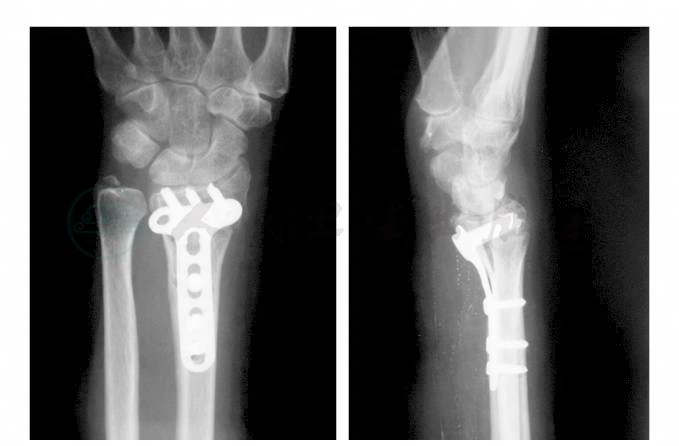

术后24小时拔除伤口引流条。术后第1天开始指间关节和掌指关节主动活动,同时配合肢体静脉泵消肿治疗。术后第2天减少伤口敷料,包扎后开始腕关节功能练习,由患者健侧手辅助被动活动逐渐过渡到患侧腕关节的主动活动。到伤口拆线时患侧腕关节应达到正常的活动范围。术后复查X线片,见内固定位置良好(图2)。

图2 术后腕关节正侧位X线片